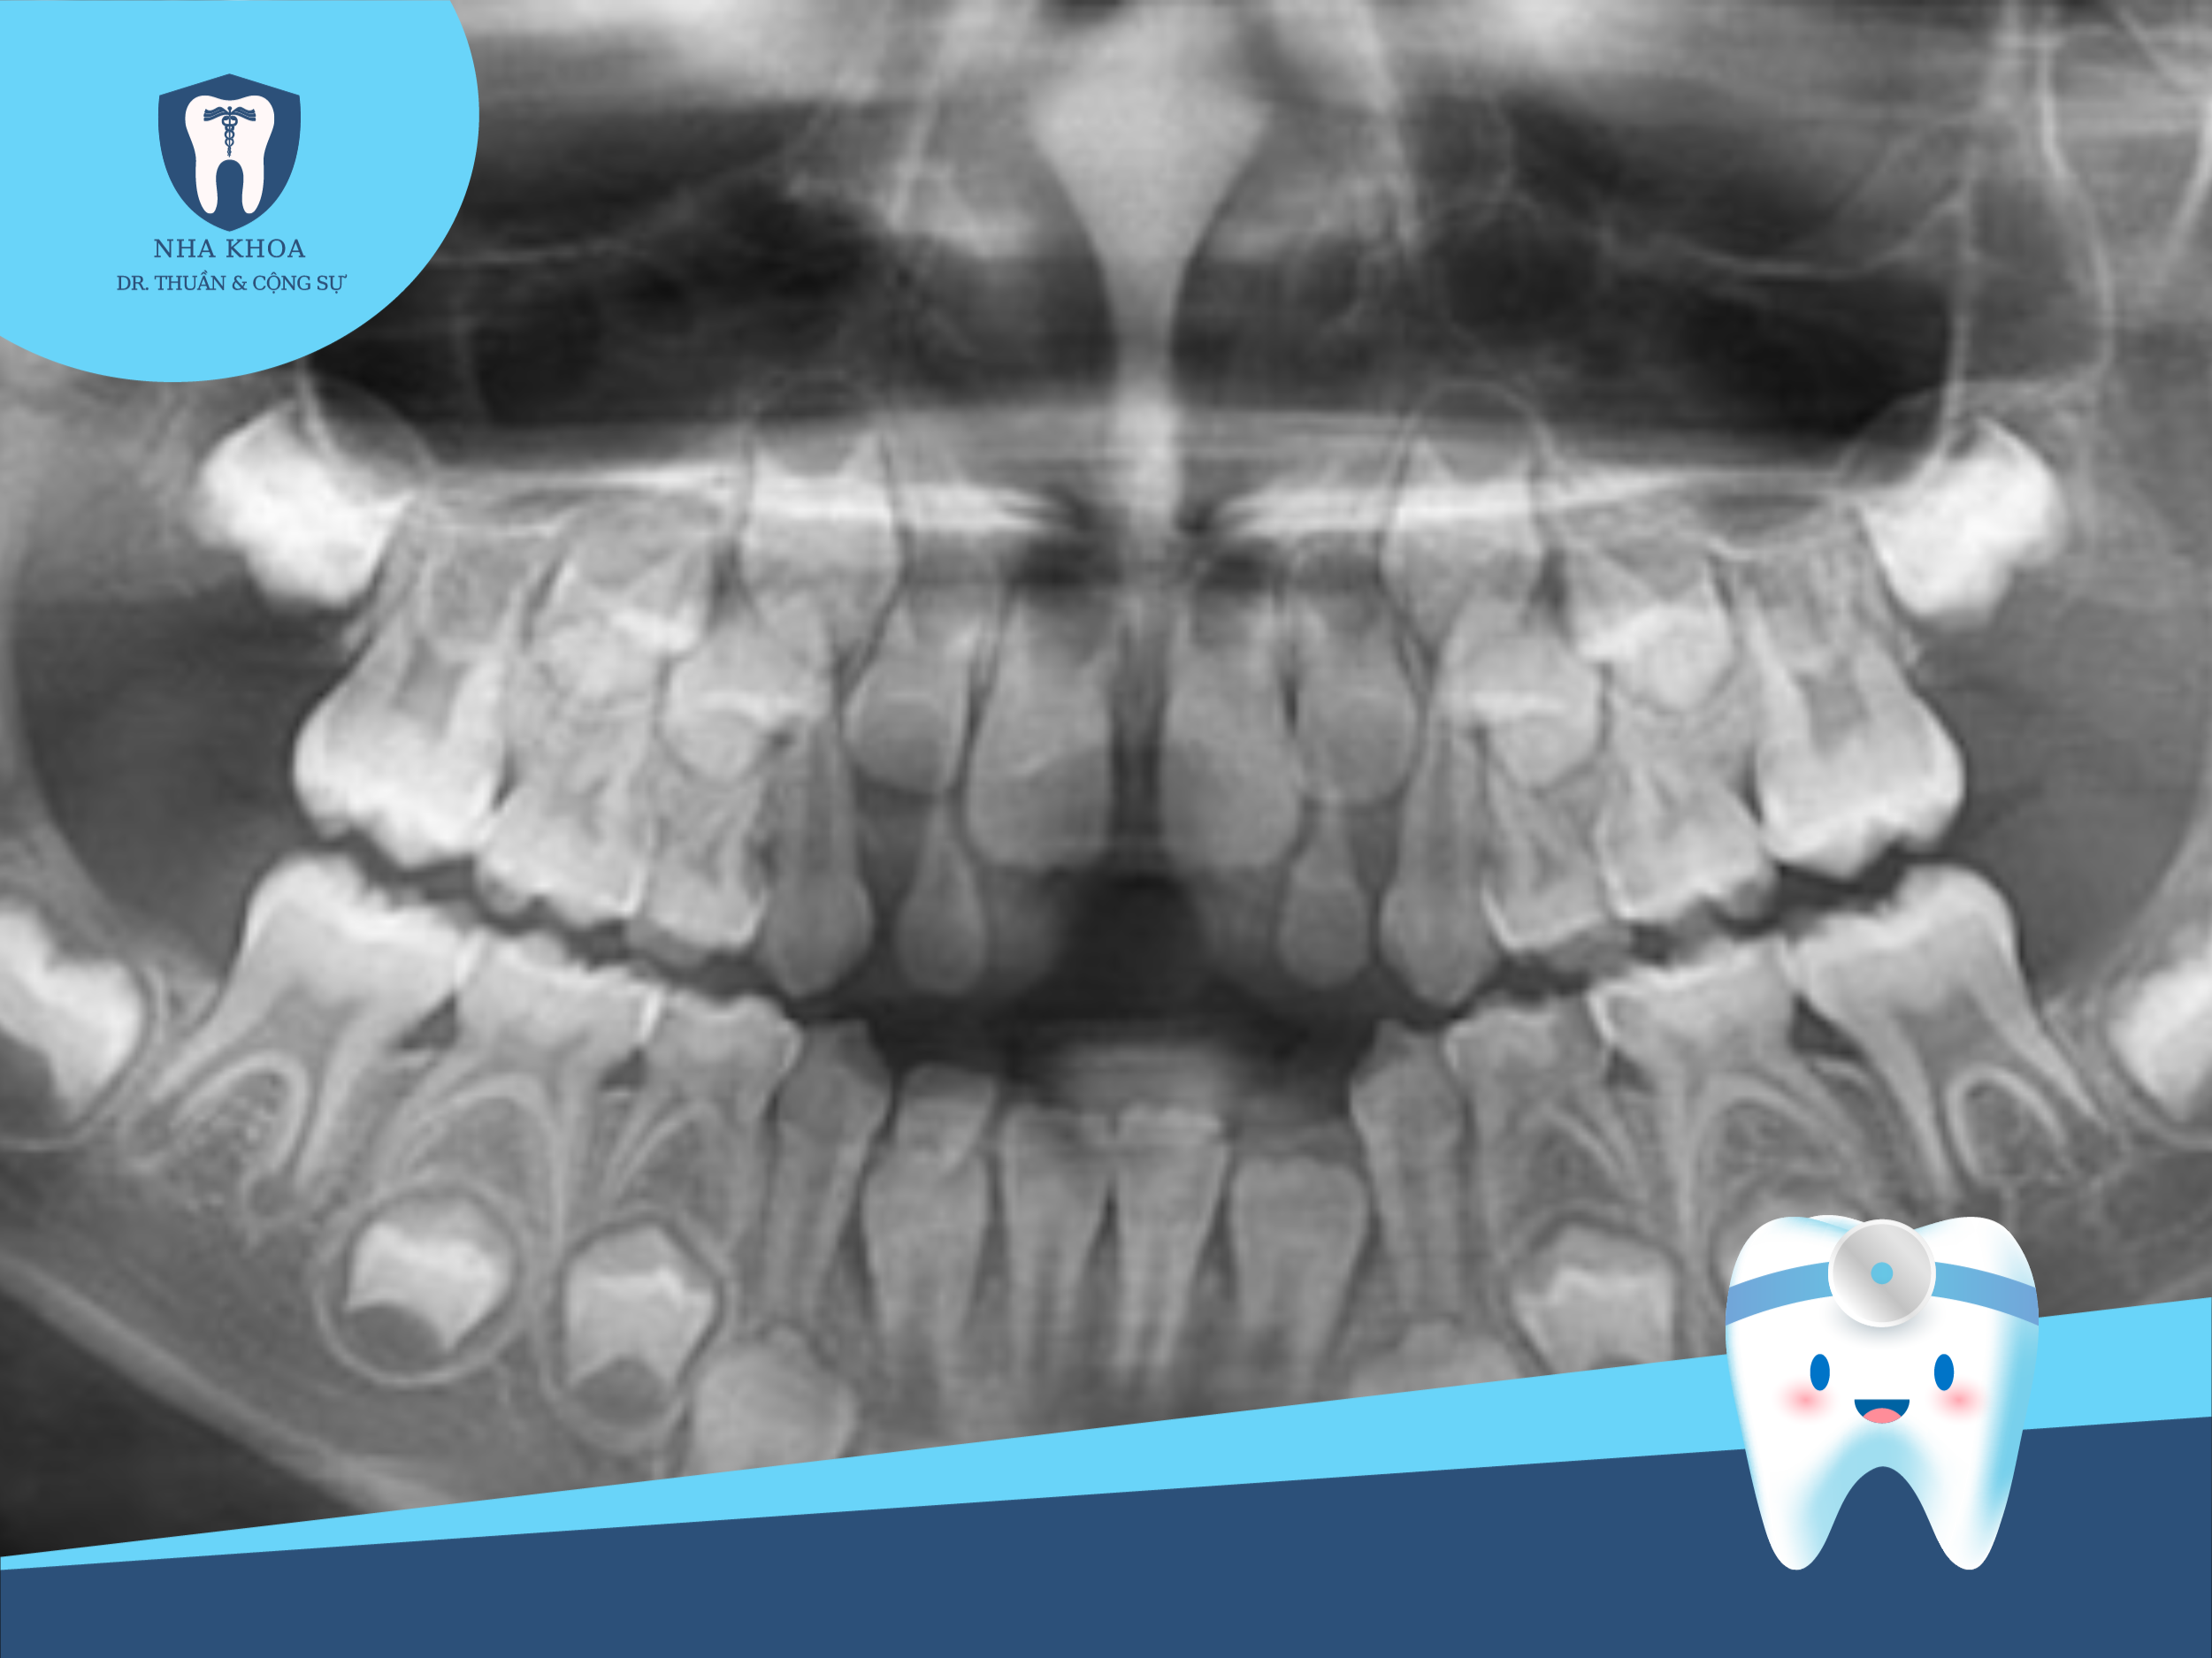

Hình ảnh 3: Để có thể chẩn đoán, lên phác đồ điều trị thích hợp với từng đối tượng bác sĩ rất cần những hình ảnh cụ thể, tổng quát từ phim XQ.

Dù là niềng răng mắc cài kim loại thường, niềng răng mắc cài tự động hay niềng bằng máng trong suốt thì tổng thời gian hoàn thiện và đủ điều kiện tháo niềng cũng không hề ngắn (thường là tính bằng năm). Cho nên, để có thể chẩn đoán, lên phác đồ điều trị thích hợp với từng đối tượng bác sĩ rất cần những hình ảnh cụ thể, tổng quát.

- Phim toàn cảnh (Panorama): Phim XQ này sẽ cho thấy tình hình tổng quát nhất về hàm răng và khảo sát thêm được các bệnh lý răng, bệnh lý xương hàm của bạn.